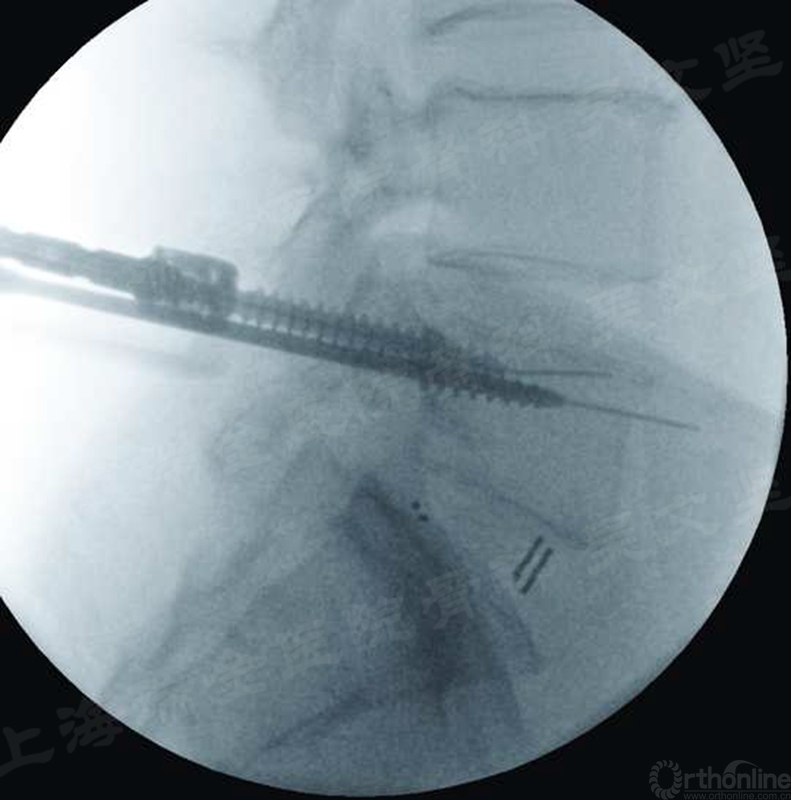

Jamshidi针穿刺完成以后,即可拔出内芯,插入导针,然后进行攻丝和螺钉植入等操作。导针是经皮椎弓根螺钉植入的重要导引,但导针如果使用不当,轻者可能因为导针拔出而延长操作时间,严重者可能因为导针穿破椎体前方导致血管和内脏损伤等严重并发症。(图4)

图4 导针穿破椎体前方进入腹腔

手术医生要了解、熟悉厂家提供的导针的特点。导针有尖头和钝头之分,有光头和螺纹头的区别,手术医生应该根据情况选择合适的导针。我个人选用的是钝的螺纹头导针,主要考虑选择钝头导针可以避免尖锐的针头穿破椎体前壁,螺纹头增加与松质骨的摩擦力,减少导针拔出的风险。

在攻丝、取出丝攻、螺钉植入的过程中,丝攻等器械应该与导针同轴,否则导针可能随着器械进出而突破椎体前壁或拔出。为了避免这种情况发生,可以一手操作,另一个手把持导针,确保操作时导针不会发生转动、进出,一旦出现导针活动,应该立刻调整操作器械的方向。(图5)

图5 一手把持导针,一手操作